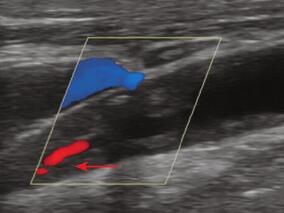

1小时条评论1 病例简介 例1,患者男,60岁。主因头晕不适伴左上肢无力1周于2009年12月15日于本院神经内科就诊。患者于就诊前1周日常活动中出现头晕不适,无意中发现左上肢无力,休息数小时后头晕症状有所缓解,但仍感左上肢轻微无力。初次发作后未予重视,未立即到医院就诊,...